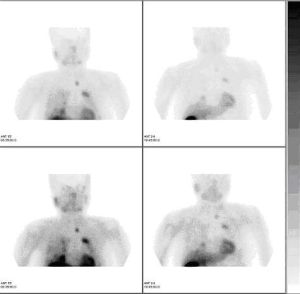

甲狀腺核素掃描

根據結節對放射性核素的攝取能力分為“熱結節”和“冷結節”。“熱結節”是功能自主性甲狀腺結節,幾乎多為良性。“冷結節”則有癌的可能,但多個“冷結節”多為良性腺瘤或結節,此外,若結節內有出血或囊性變,也可表現為“冷結節”。